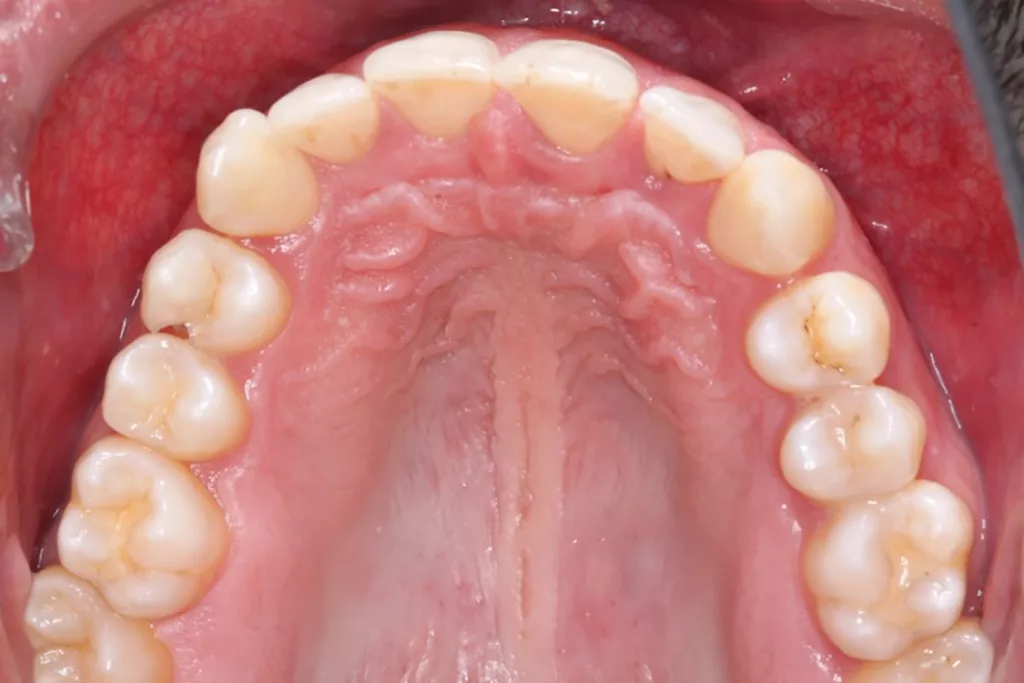

Robuste Evidenz aus aktuellen großen bevölkerungsbasierten Studien zeigt eine Überlegenheit der Effektivität elektrischer Zahnbürsten gegenüber Handzahnbürsten. Darüber hinaus legen systematische Übersichtsarbeiten und In-vitro-Studien einen zusätzlichen Effekt – die Putzwirkung auch ohne direkten Borstenkontakt durch unterschiedliche Strömungsphänomene – bestimmter elektrischer Zahnbürsten (Schallzahnbürsten) nahe. Laboruntersuchungen zeigen aber auch große Unterschiede der untersuchten Zahnbürsten hinsichtlich der Effektivität der Biofilmreduktion. Das bedeutet, dass in der Klinik (Abb. 7–9) in aller Regel eine Empfehlung für elektrische Zahnbürsten und (!) geeignete Hilfsmittel für die Zahnzwischenraumpflege vorliegen sollte.